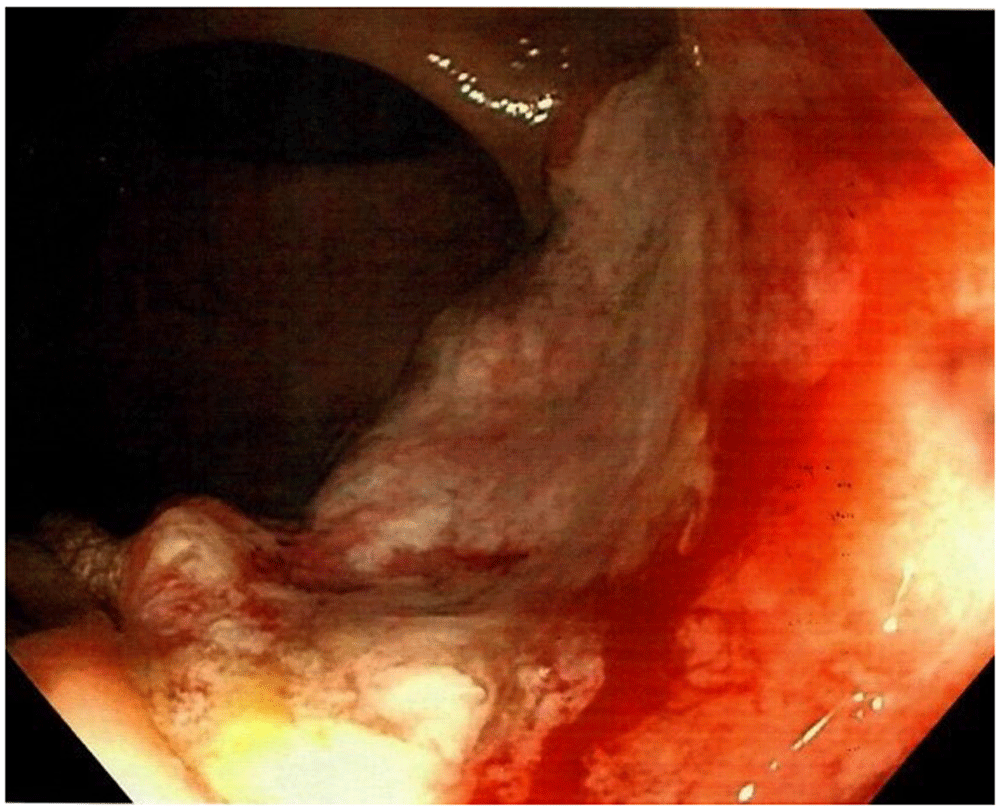

A 58-year-old Caucasian man with no prior medical or surgical history was admitted to the emergency department after referral from his general practitioner. The patient complained of constant diffuse abdominal pain for two days with exacerbation upon movement. He had had fever for one day. His stool was normal without blood and there was no nausea or vomiting. The patient had no family history of colorectal cancer. The abdominal examination revealed direct tenderness in both lower quadrants. The DRE that was performed by the newly qualified doctor on call was without palpable tumors. Laboratory blood tests showed elevated C-reactive protein (110 mg/L [normal value less than 3 mg/L]). All other blood tests were normal. An acute computed tomography (CT) scan of the abdomen showed signs of acute appendicitis. A diagnostic laparoscopy confirmed the diagnosis macroscopically and an uncomplicated laparoscopic appendectomy was performed. The patient was discharged the following day. The postoperative standard histopathologic examination of the appendix showed acute non-perforated appendicitis and, surprisingly, a 13 mm T1 goblet cell adenocarcinoma in the apex of the appendix with tumor-free resection margins. The patient was informed and underwent a new CT scan of the thorax and abdomen. The only new finding on the repeated CT scan was rectal wall thickening. The patient was discussed at a multidisciplinary team conference where it was decided to perform a colonoscopy due to the rectal wall thickening and thereafter a laparoscopic right hemicolectomy due to the tumor in the appendix. Prior to the colonoscopy, the endoscopist, who is an experienced colorectal surgeon, performed a DRE. The endoscopist palpated the distal part of a tumor in the anterior wall of the rectum seven centimeters from the anal opening. The colonoscopy showed a tumor highly suspicious for malignancy with a central depression of 25 mm (Figure 1). It was classified as National Institute for Clinical Excellence (NICE) type 3. A magnetic resonance imaging (MRI) scan staged the tumor as a T2 without metastasis to lymph nodes or distant metastasis (Figure 2). The histopathologic examination of the rectal lesion showed a primary signet ring cell carcinoma that was histologically distinct from the appendiceal tumor. Hence, the patient had two primary synchronous tumors. Eventually, the patient was treated with simultaneous laparoscopic right hemicolectomy and low anterior resection. Figure 3 presents a timeline of the events. The postoperative course was complicated by an anastomotic leakage of the colorectal anastomosis. The leakage was treated with endoscopic vacuum-assisted closure. After surgery, the patient received adjuvant chemotherapy.

Figure 2. Magnetic resonance imaging scan showing the rectal tumor.